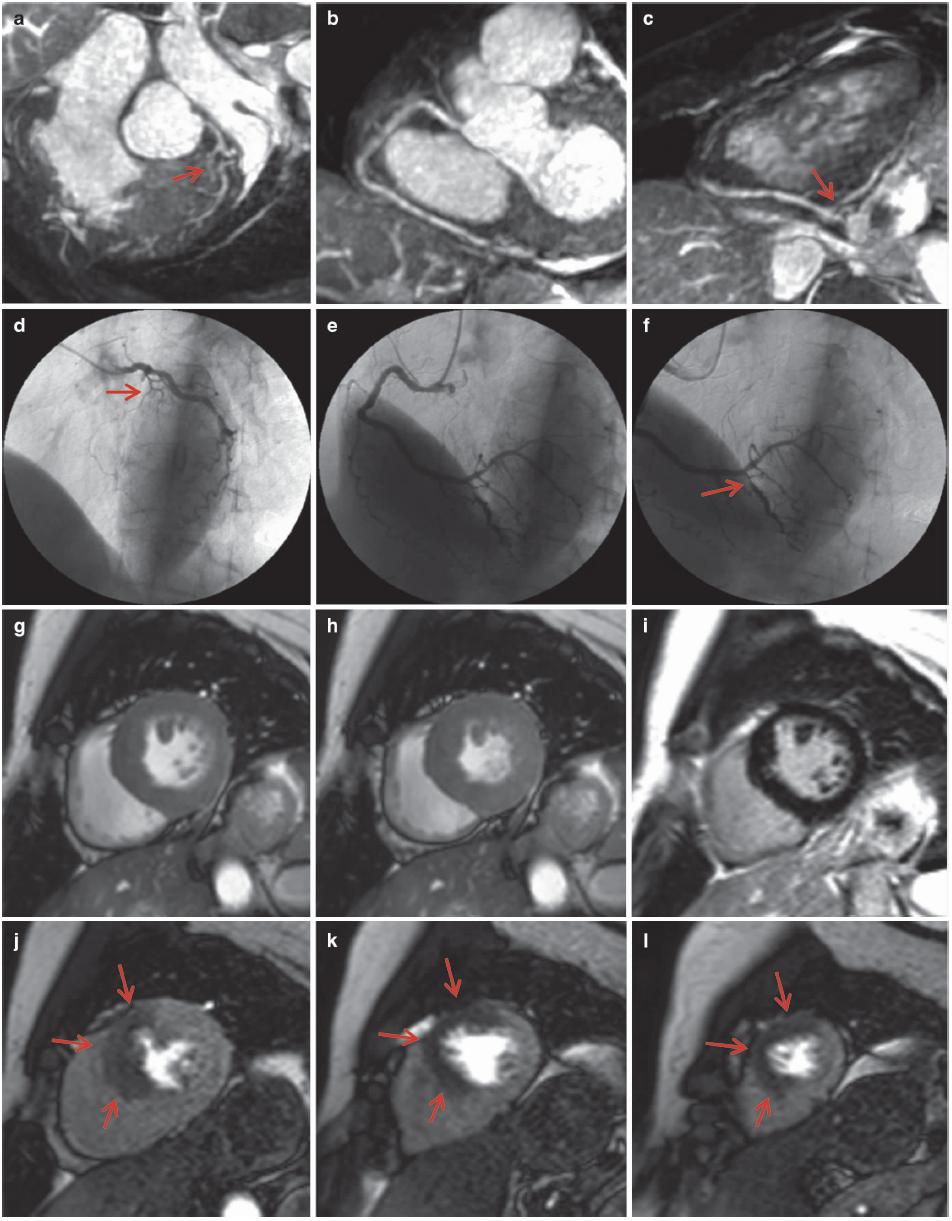

图7.6 心肌缺血,LAD明显狭窄。患者男性,40岁,胸痛。1.5T MR获得非对比增强的三维CMRA图像,采用稳态自由进动(SSFP)序列、导航回波门控、T2预扫描、光谱预饱和、反转恢复脂肪饱和(TR/TE,4.6/2.3ms;翻转角度,90°;SENSE因子4;FOV 280mm×280mm×120mm;采集矩阵256×256×80;重建矩阵512×512×160)。

(a)全心冠状动脉MR血管造影MIP图像显示LAD近段重度狭窄或闭塞(箭头)。(b,c)后降支(PDA)也有明显狭窄。(d-f)冠状动脉MR血管造影和冠状动脉造影(箭头)之间有良好的一致性。(g)舒张末期的短轴电影MR图像,(h)收缩末期未见明显的区域性室壁运动异常。(i)晚期钆增强MR图像未见心肌瘢痕。(j-l)负荷和灌注MR图像显示前间壁严重缺血(箭头),与LAD供血区对应。